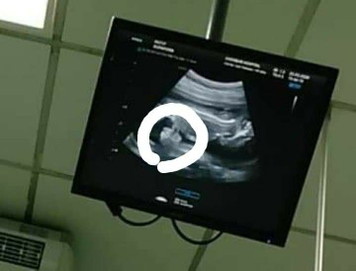

Gastroschisis

ลูกเรามีไส้ทะลักออกมาอยู่ข้างนอกเกิดจากอะไรคะแล้วถ้าคลอดลูกเราจะกลับมาปกติมั้ยคะตอนนี้เราเครียดมากๆเลยค่ะ

เราเป็นเคสนี้ค่ะ คำตอบจากหมอ คือเด็กฟอร์มตัวไม่ดีในช่วง1-3เดือนแรก เหมือนสร้างไม่เสร็จ ด้วยอาการแม่ด้วยหรือป่าวไม่แน่ใจ แม่เป็นไทรอยด์ เครียดหนักมาก ร้องไห้บ่อย แต่หมอบอกว่า ผ่าตัดตอนคลอดแล้วได้ แต่ของเราน้องจากไปตอน8เดือนในครรภ์ คุณแม่อย่ากังวลนะ ด้วยร่างกายเราด้วยแหละ สู้ๆ นะค่ะ